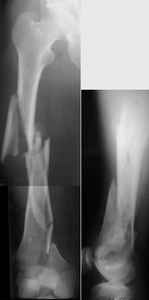

I presented a series of ~25 such cases at EuroTrauma'2004. Many cases were discussed here. I attach am example. Look also recent cases at http://www.hwbf.org/hwb/conf/alex58/scfx.htm,

THX, initial images are

1,

2.

At that moment we had in stock only the 10 mm solid nails so of course there was no idea about early weight bearing. But it was quite enough for early knee ROM excersises (see attached). Two locking screws through the distal block provided that.